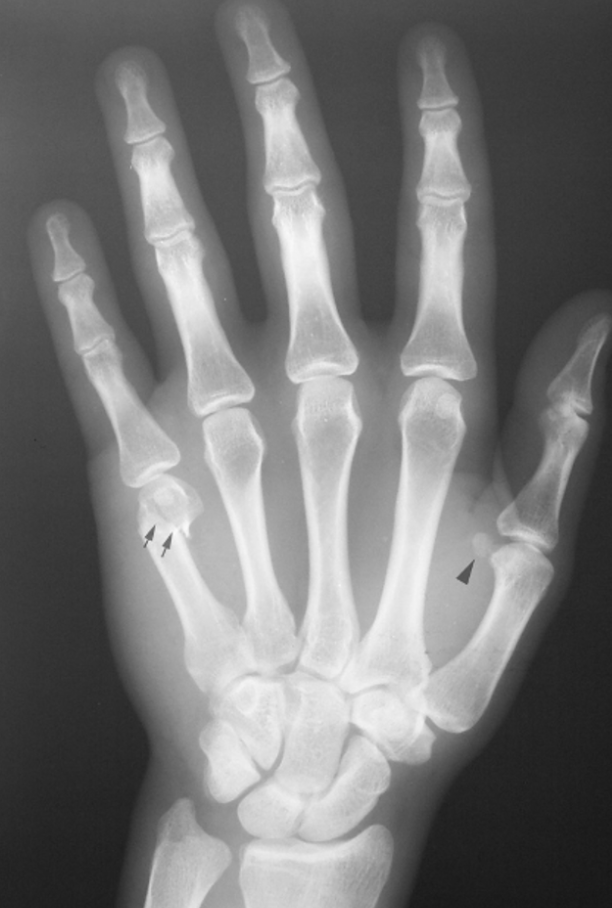

What is a Bennet’s fracture?

Intra-articular fracture at the base of the 1st metacarpal (thumb)

Axial compression on a slightly flexed CMC joint - so occurs when falling on outstretched hand (FOOSH) or in boxing

In Bennet’s fractures - the metacarpal of the thumb is displaced

Displacement due to proximal pull from abductor pollicis longus (therefore unstable)

What is a Boxer’s fracture?

Fracture of the neck of the metacarpal

Usually the little or ring finger

Often volar (palmar) displacement